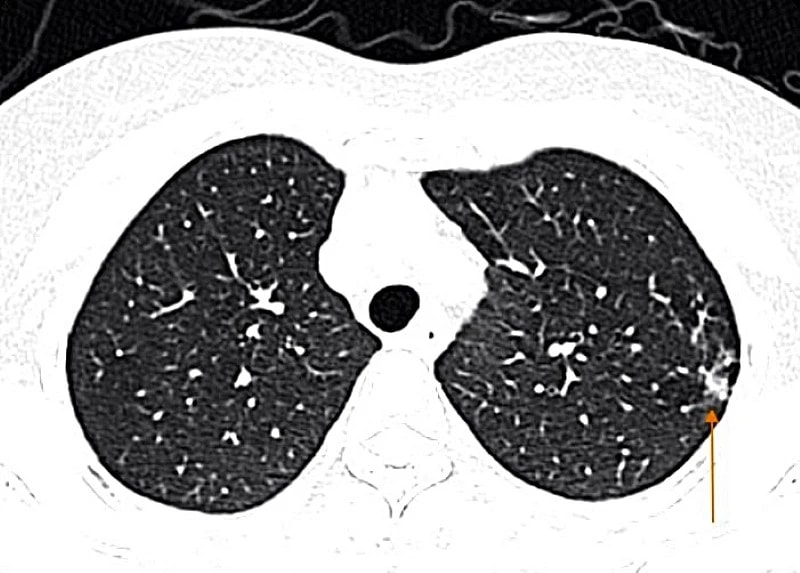

Tự mua thuốc cảm cúm, người phụ nữ nhập viện vì biến chứng viêm phổi: Bác sĩ cảnh báo!

Ngày 8.2, Bệnh viện Đa khoa MEDLATEC thông tin về việc tiếp nhận trường hợp một người phụ nữ nhập viện ngay trong đêm vì biến chứng viêm phổi do mắc cúm A. Điều đáng nói là bệnh nhân nghĩ chỉ cảm cúm thông thường, nên tự ra hiệu thuốc mua thuốc uống và bị diễn tiến nặng kèm theo nhiều biến chứng nguy hiểm.